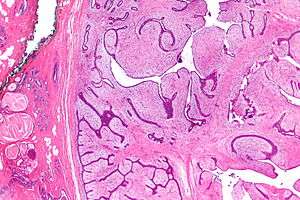

![]() | |

| Micrograph of a phyllodes tumor (right of image) with the characteristic long clefts and myxoid cellular stroma. Normal breast and fibrocystic change are also seen (left of image). H&E stain. | |